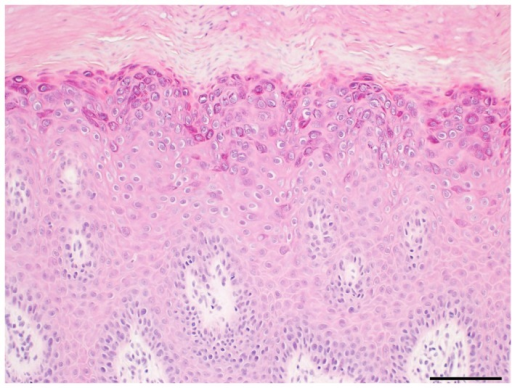

피부의 편평사마귀는 HPV 3, 10, 28, 49번 에서 주로 생깁니다. 가볍게 생각하면 피곤할 때 생기는 입술주변의 헤르페스 감염 처럼 생각해 볼 수도 있지만, 감염력이 강할 수 있기 때문에 반드시 병변이 있을 때에는 레이저 등으로 사마귀 균사를 제거해야합니다.

쉽게 대표적으로 보이는 편평사마귀와 좁쌀 여드름의 구분하는 방법은 편평한 융기가 있는지 확인하는 것 입니다.

본론으로 돌아와서, 편평사마귀는 말그대로 무증상이면 크게 문제가 되지 않지만 툭 튀어나온 '편사' 가 생기게 되면 외과적이나 레이저로 제거를 해서 바이러스의 추가적인 감염을 막는 것이 중요합니다.